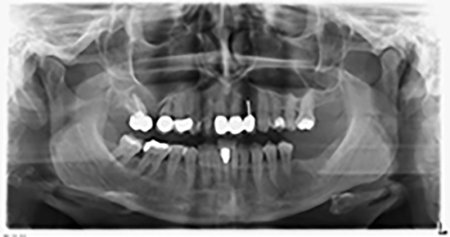

La paziente, 59 anni, presenta un caso di parodontite avanzata e descrive una sensazione di fastidio e scarsa sensibilità gustativa dal primo quadrante in direzione distale. L'esame clinico rivela tasche parodontali generalmente diffuse e un'atrofia ossea molto avanzata nelle regioni 16 e 14. L'esito è confermato dalla radiologia (fig. 1). Non è possibile salvare i denti 16 e 14.